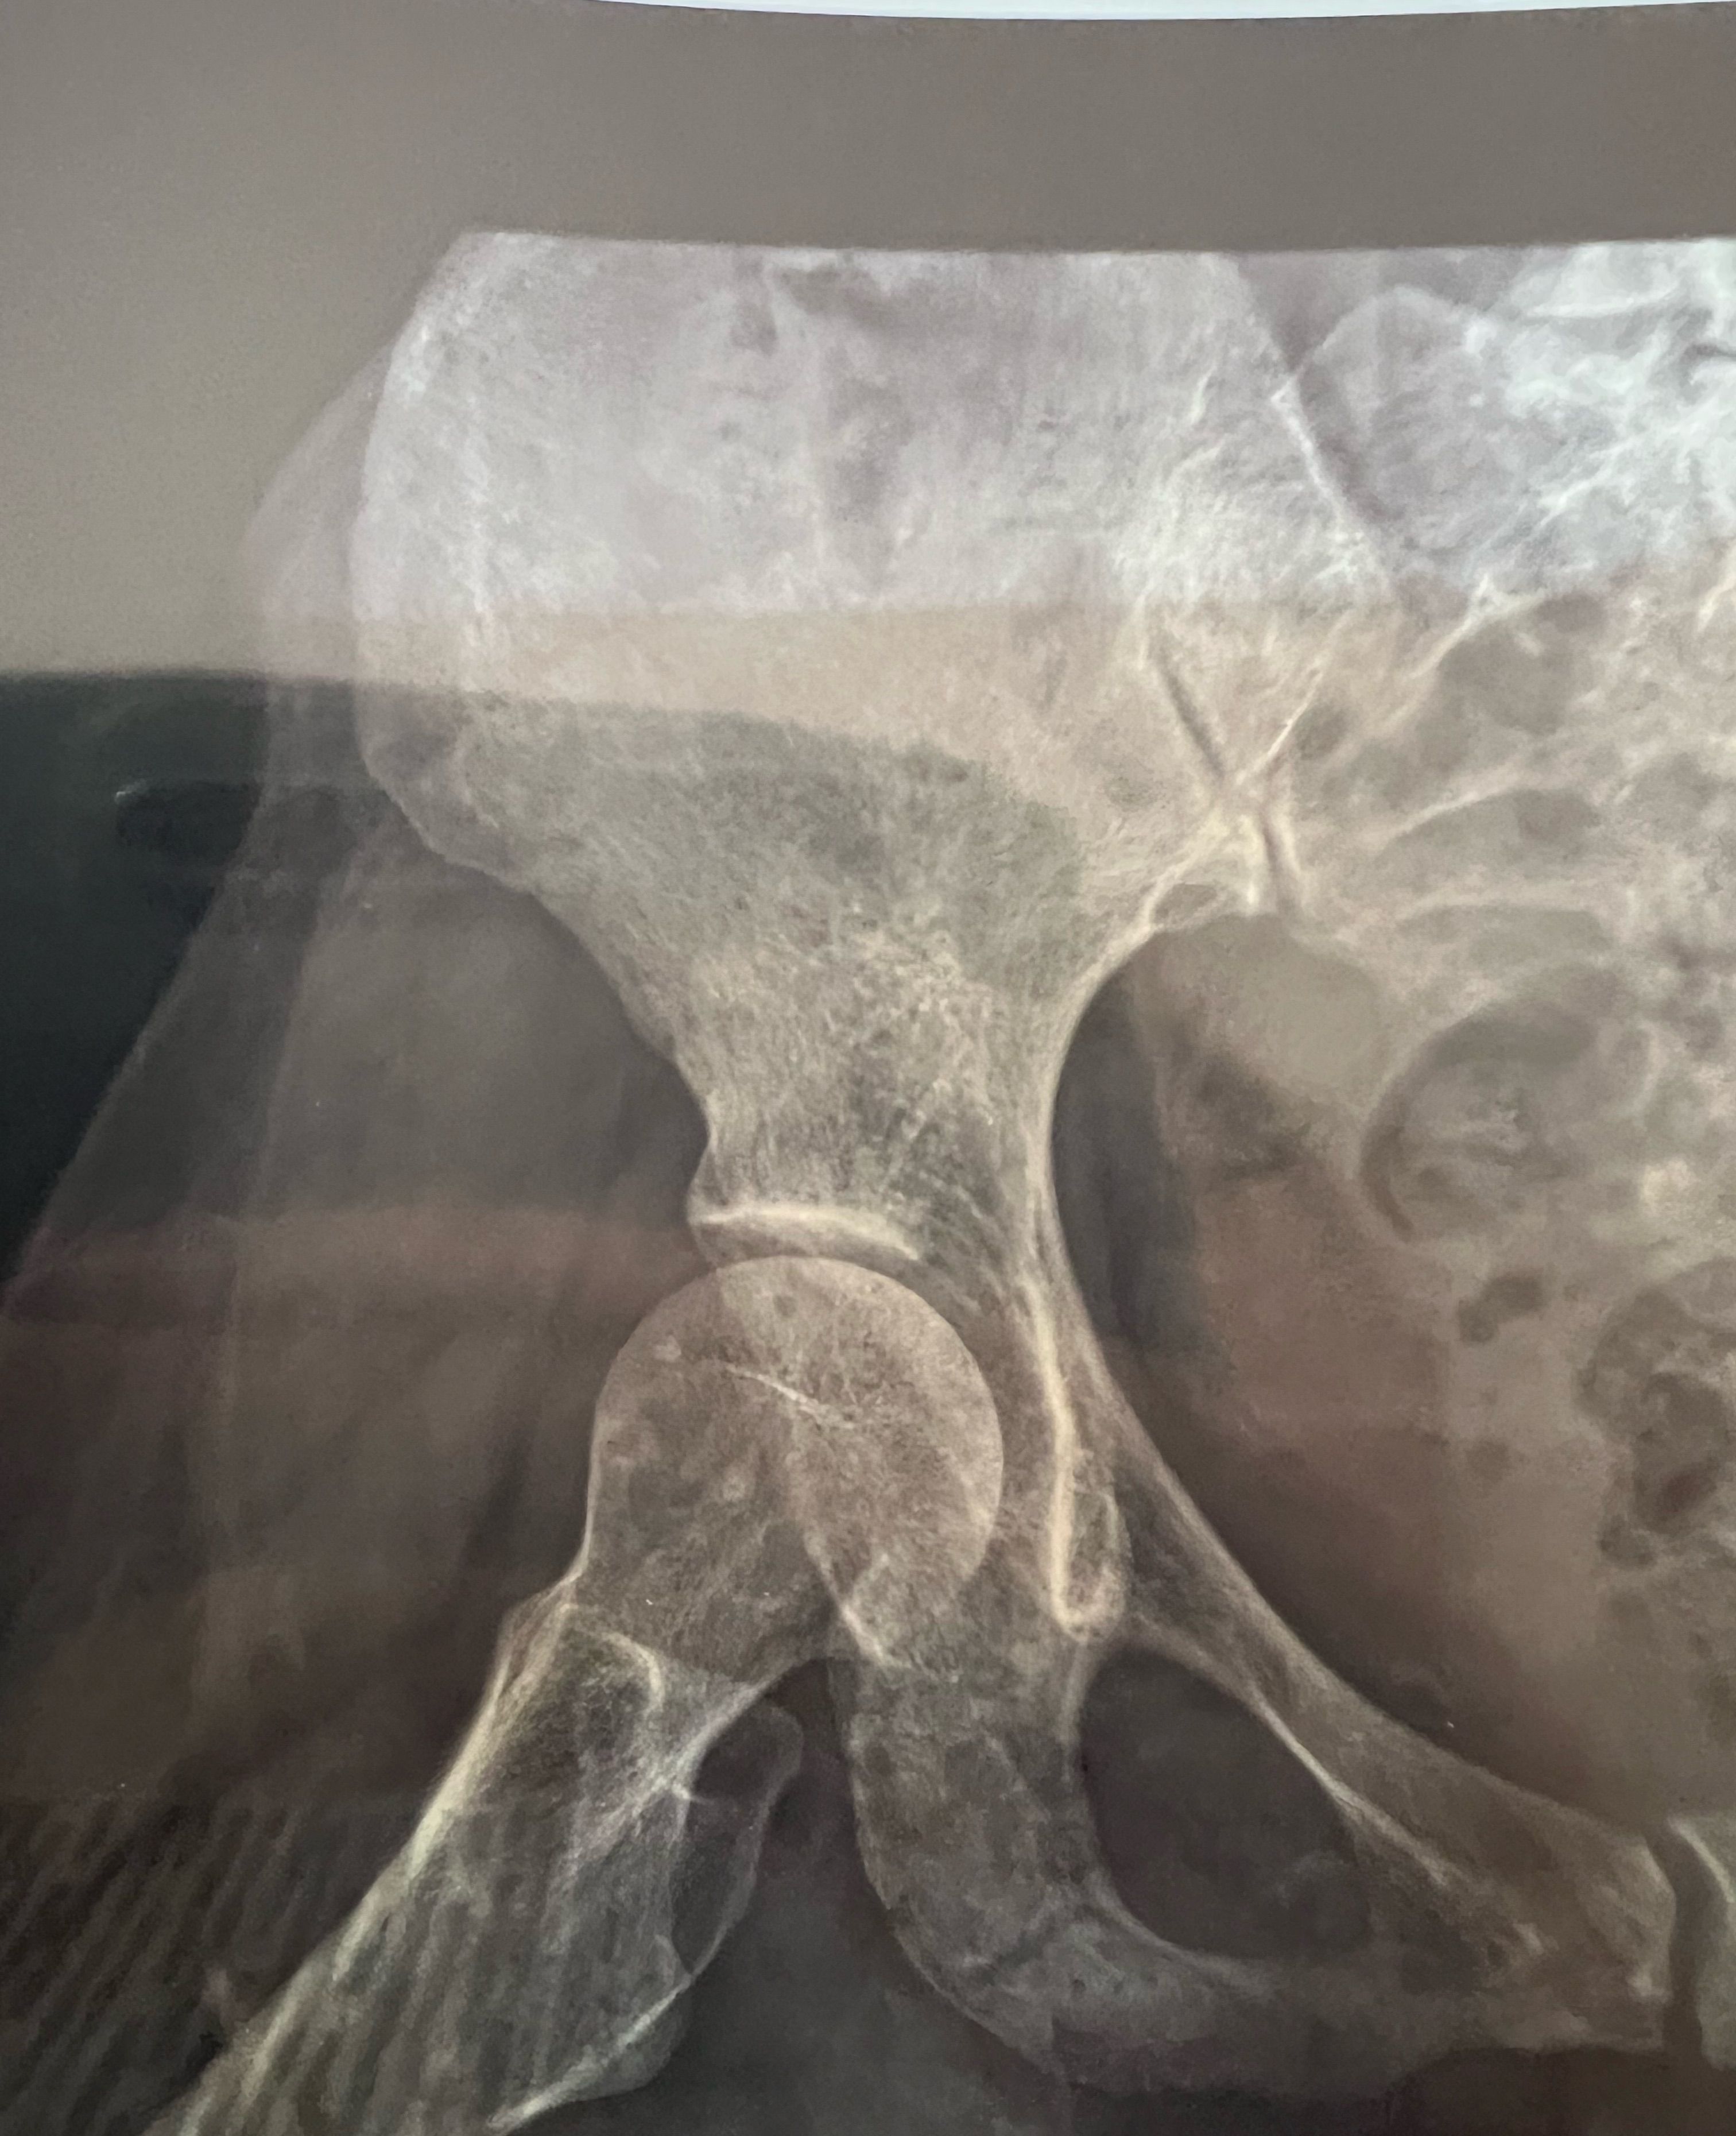

pelvic bone problems

35 years old female falling down from high place